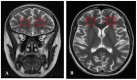

Schizophrenia is characterized by complex metabolic dysregulations and their consequences. Until now, numerous theories have explained its pathogenesis, using a spectrum of available technologies. We focused our interest on lipid profile-periphery high-density cholesterol level and lipoproteins in the human brain and compared magnetic resonance imaging (MRI) scans of patients with schizophrenia and the healthy group. Detailed analysis of biochemical parameters was performed using magnetic resonance spectroscopy. Our study aimed to reveal correlations between periphery high-density lipoproteins levels and lipoproteins in the brain, depicted in MRI scans, and parameters of peripheral oxidative stress expressed as paraoxonase. Patients with schizophrenia have decreased levels of high-density lipoproteins, low paraoxonase activity, and slightly raised sodium in the blood. Positive significant correlations between serum high-density cholesterol and anterior cingulate cortex, unique brain area for schizophrenia pathophysiology, MR spectroscopy signals, and diffusion have been revealed. To our knowledge, this is the first study to describe the effect of an anterior cingulate disorder on high-density cholesterol levels on the development of schizophrenia.